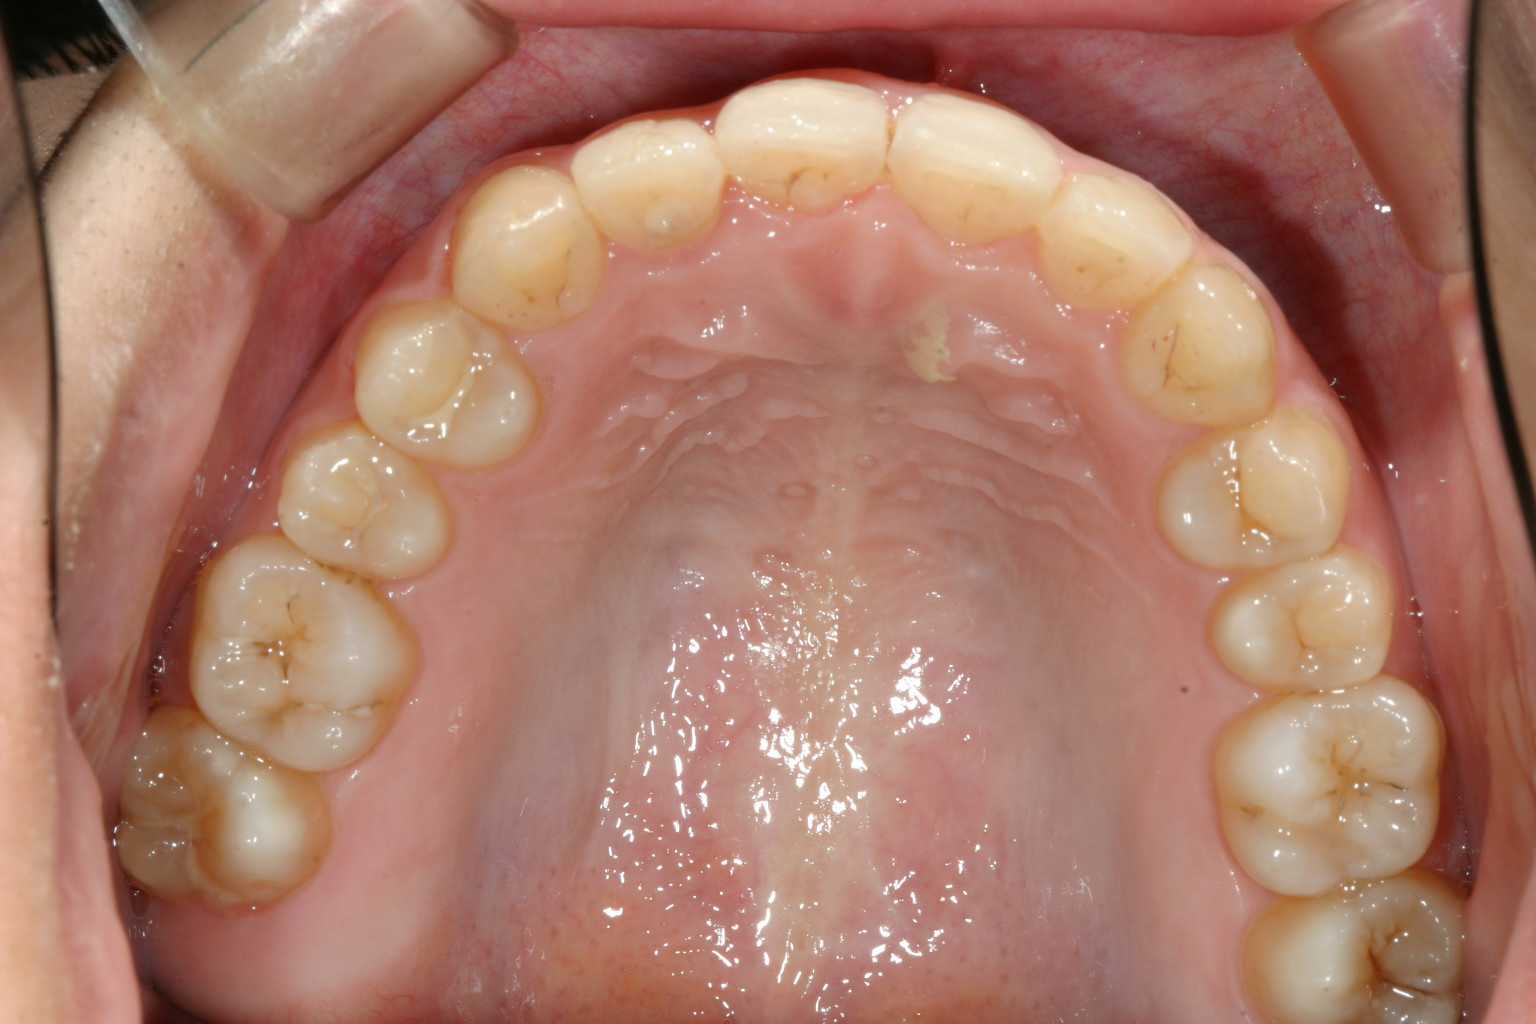

上顎は綺麗なアーチに改善されました。

下顎も綺麗なアーチになっています。